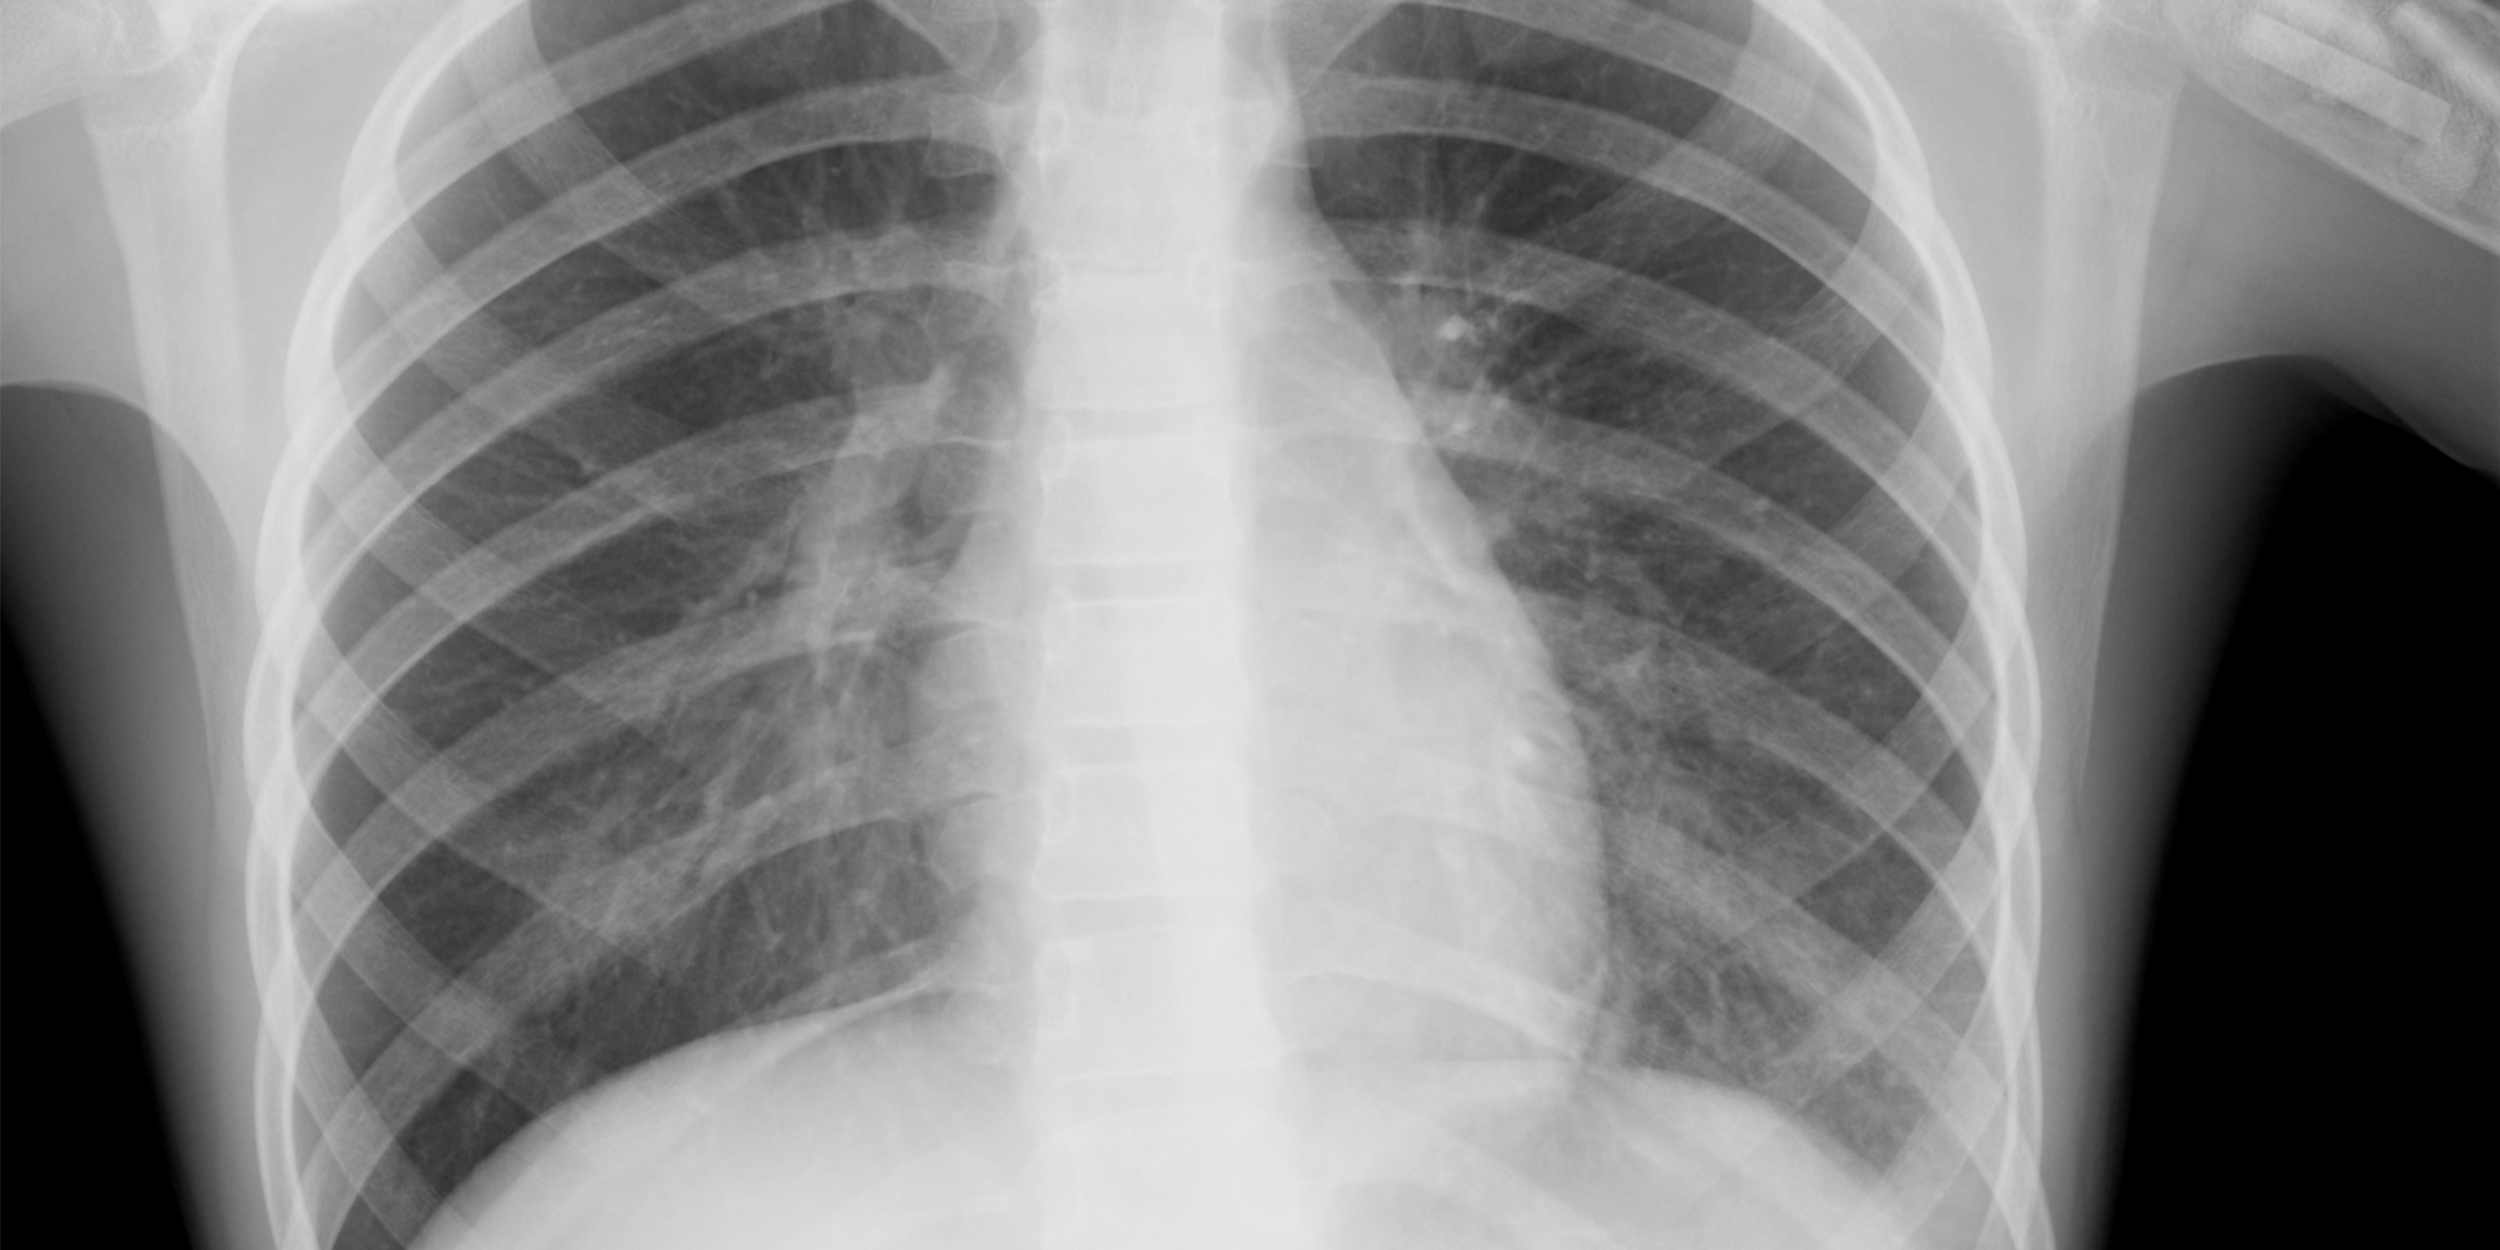

Диагностика заболеваний

Когда возникает боль в левой части грудной клетки, многие обращаются к терапевту или кардиологу. В зависимости от истории болезни и сопутствующих симптомов, диагностику могут проводить гастроэнтерологи, неврологи, пульмонологи и маммологи. Для выявления причины дискомфорта могут быть назначены следующие исследования:

- общий анализ крови и мочи;

- рентгенография;

- ультразвуковое исследование;

- компьютерная томография;

- магнитно-резонансная томография;

- дуплексное сканирование сосудов;

- ангиография;

- электрокардиография.

При проведении диагностики важно установить, как боль связана с физической или эмоциональной нагрузкой. Учитывается, проходит ли она после приема Нитроглицерина или обезболивающих, а также связана ли с приемом пищи, дыханием, кашлем или временем суток.